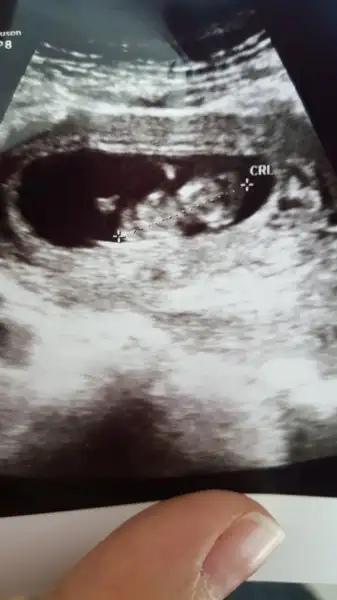

ben baska arkadasa ultrason goruntusunden genital nub tahmini yapmistim tutmus. Ama bir turlu kendiminkini bilemiyorum ya nasil bir kisiligim var anlamadim gitti :KK45:

IMG-20180103-WA0001.webp bu ne sence 10 haftalik tam